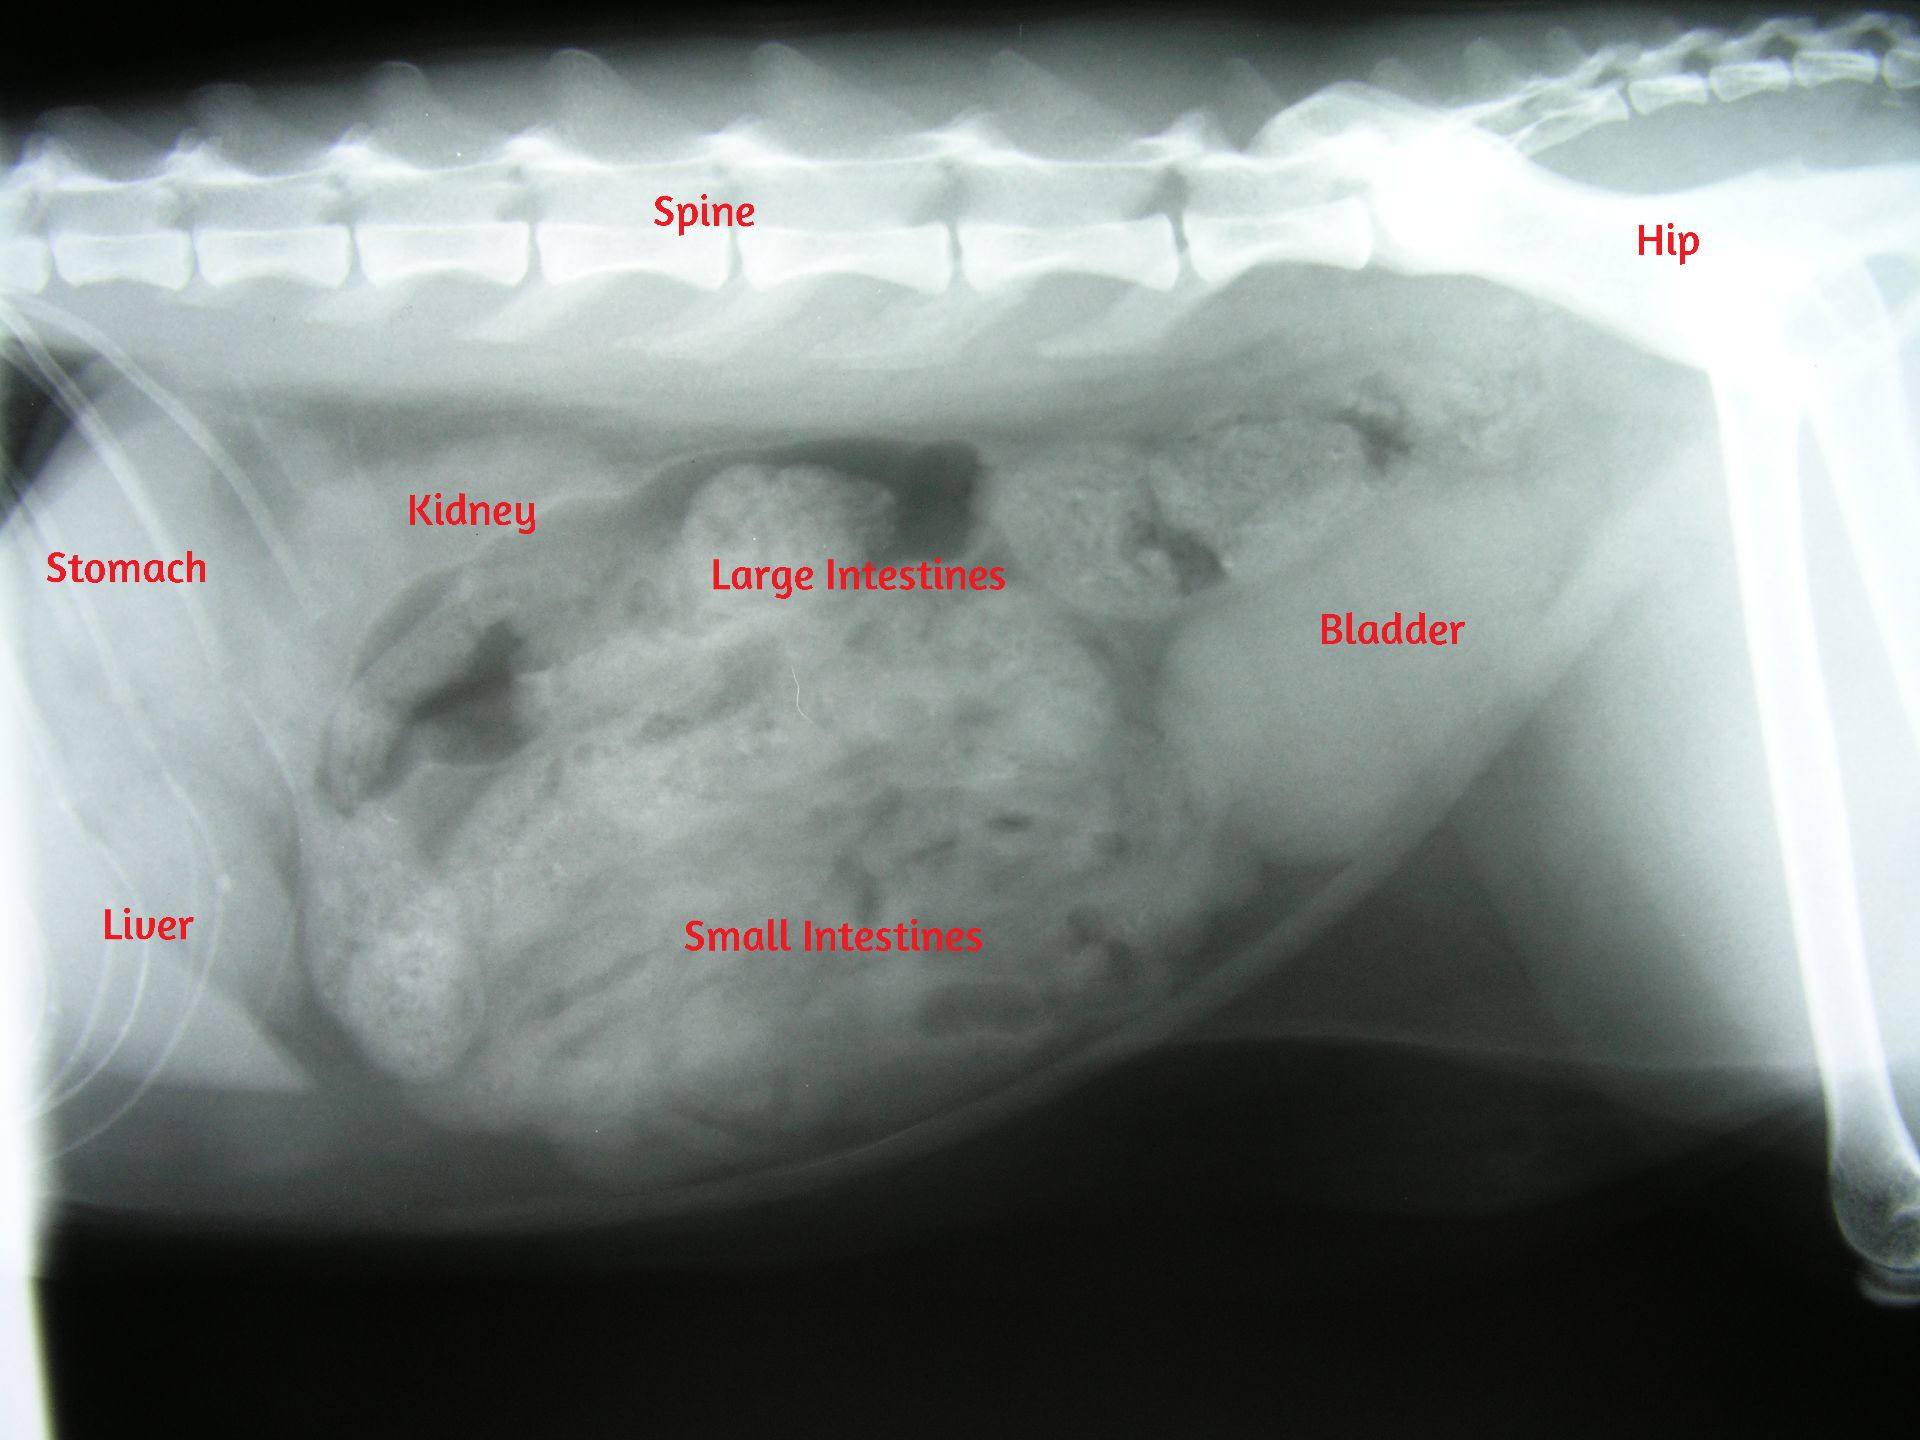

Normal lateral abdomen X-ray showing the normal positioning of the organs